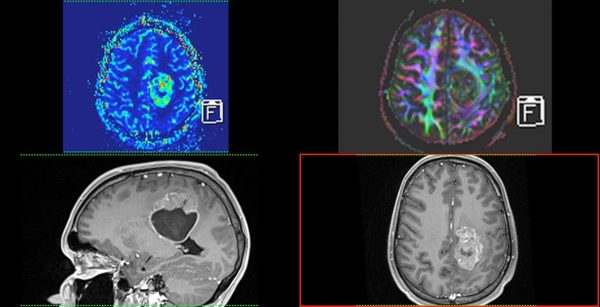

- МРТ: Створює найчіткіші зображення м’яких тканин, органів та судин. Без використання шкідливого випромінювання, тому також підходить для візуалізації вагітних, дослідженні плоду.

Завдяки передовим технологіям ми маємо можливість проводити МРТ дослідження “всього тіла” (whole body)*, мультипараметричні обстеження головного мозку та простати з наявними програмами МР-трактографії (DTI), МР-спектроскопії, також виконуємо безконтрастну МР-ангіографію інтракраніальних судин, шиї; МР-холангіопанкреатографію, ентерографію, визначення перенавантаження залізом печінки.

Магнітно-резонансна томографія: Найточніший метод для дослідження мозку, хребта, суглобів та м’яких тканин. Абсолютно безпечний тому також підходить для візуалізації вагітних, дослідженні плоду. Разом КТ та МРТ показані для виявлення вроджених аномалій розвитку/патології центральної нервової, скелетно-м’язової, травної, дихальної, сечовидільної системи, статевої сфери Також показані пацієнтам та потенційним донорам при підготовці до трансплантації,

- Магнітно-резонансна томографія: Siemens MAGNETOM Aera (1,5 Тл)